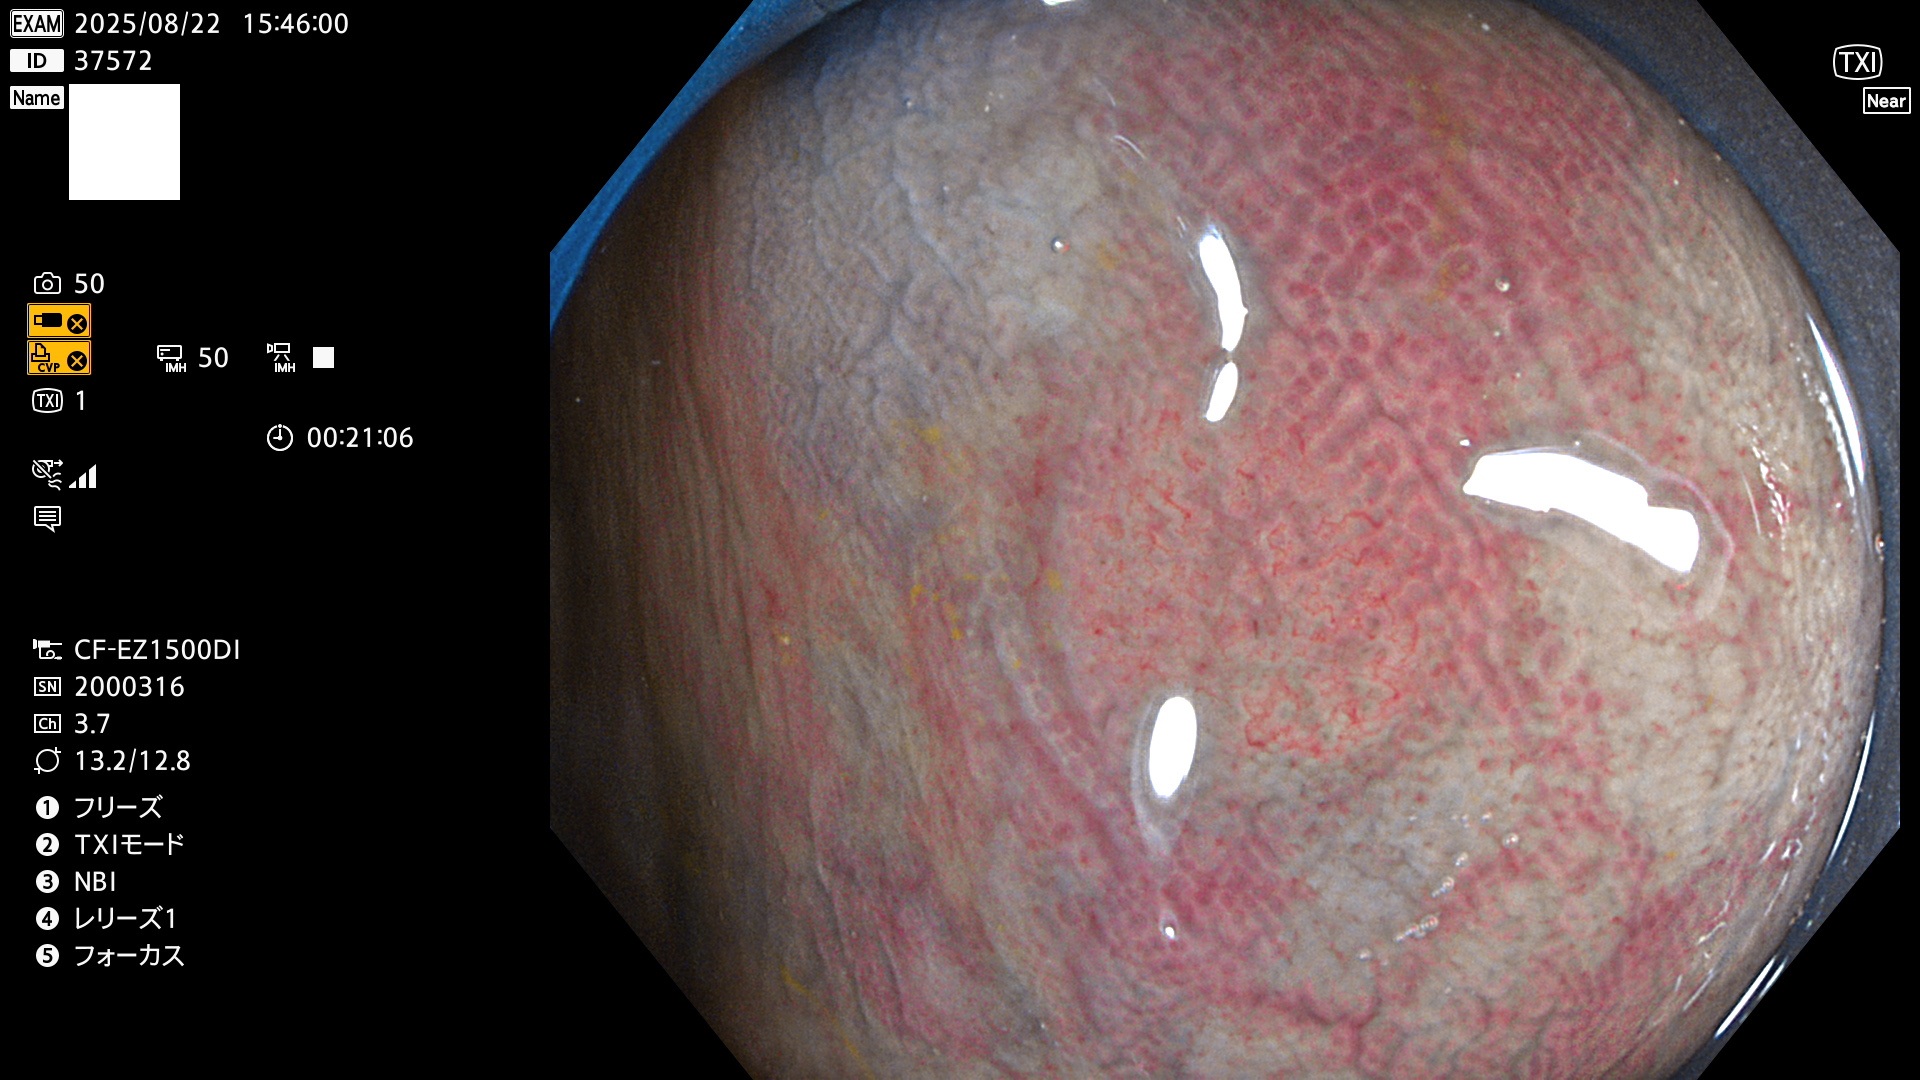

完全に平坦な物をUb、陥凹している物をUcと呼びます。Ubは認識が困難で、Ucはびらん(炎症)と紛らわしいために見落とされやすく、「内視鏡後・大腸癌」の原因になります。

毎週の検査(木・金・土・日)に発見されたUbとUc型・腺腫を、その週の日曜の夜にUPし1週間、提示します。

2025年8月21日〜8月24日の4日間(30件)5個 (Uc_ADR=3個/35人=14%)